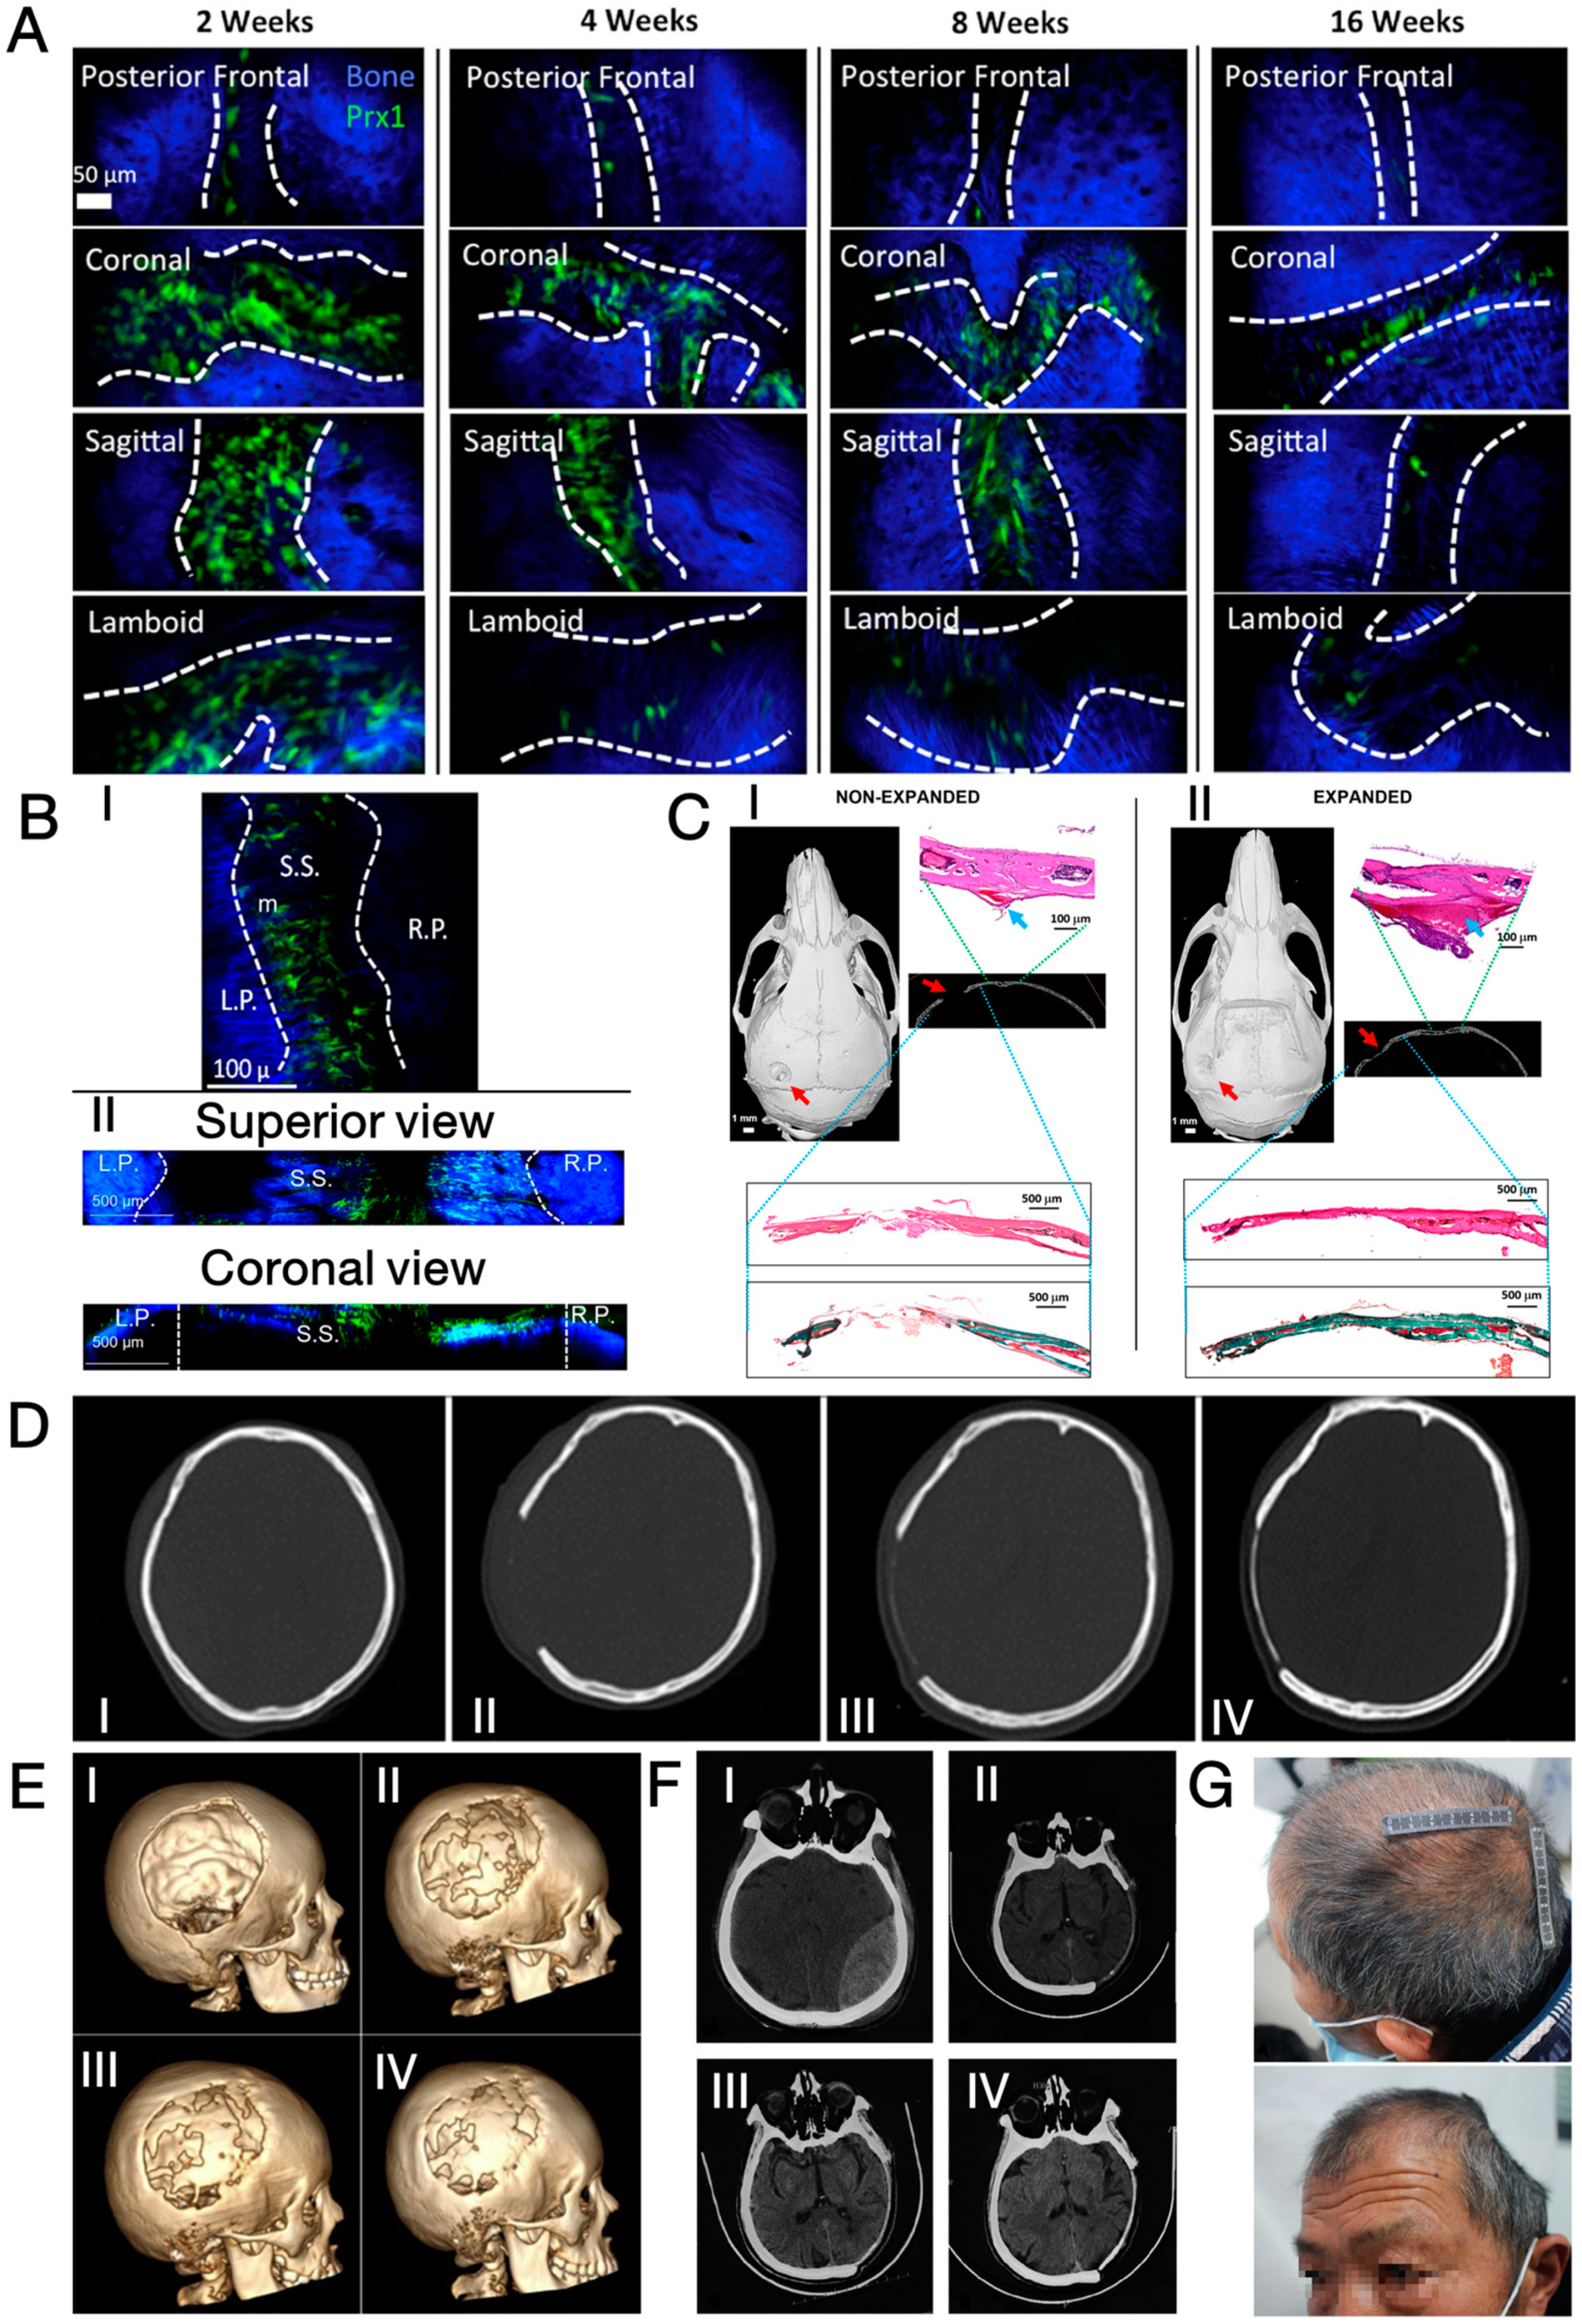

3.2. Mineralised Collagen

- Cui, F.-Z.; Li, Y.; Ge, J. Self-assembly of mineralized collagen composites. Mater. Sci. Eng. R Rep. 2007, 57, 1–27. [Google Scholar] [CrossRef]

- Liao, S.S.; Cui, F.Z.; Zhang, W.; Feng, Q.L. Hierarchically biomimetic bone scaffold materials: Nano-HA/collagen/PLA composite. J. Biomed. Mater. Res. B Appl. Biomater. 2004, 69, 158–165. [Google Scholar] [CrossRef] [PubMed]

- Wang, S.; Yang, Y.; Koons, G.L.; Mikos, A.G.; Qiu, Z.; Song, T.; Cui, F.; Wang, X. Tuning pore features of mineralized collagen/PCL scaffolds for cranial bone regeneration in a rat model. Mater. Sci. Eng. C Mater. Biol. Appl. 2020, 106, 110186. [Google Scholar] [CrossRef] [PubMed]

- Kikuchi, M.; Itoh, S.; Ichinose, S.; Shinomiya, K.; Tanaka, J. Self-organization mechanism in a bone-like hydroxyapatite/collagen nanocomposite synthesized in vitro and its biological reaction in vivo. Biomaterials 2001, 22, 1705–1711. [Google Scholar] [CrossRef] [PubMed]